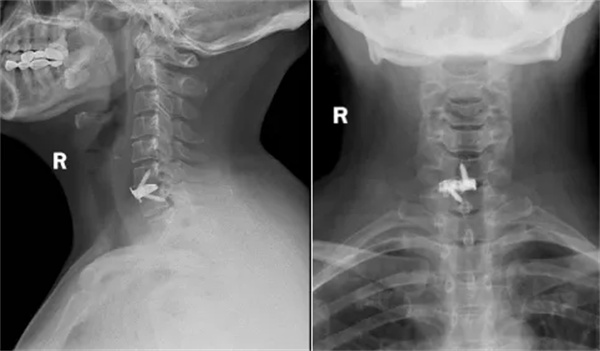

对于疑似颈椎病的患者,须就医并接受详细的病史询问和体格检查,此外,影像学检查是颈椎病诊断的重要手段,包括X光、CT和MRI等,检查可以帮助医生了解颈椎的形态及结构,判断是否存在颈椎病变及压迫神经的情况。

① X光检查:通过X光检查可以观察颈椎的排列顺序、生理曲度及骨质的改变,X光检查对于颈椎病的初步诊断和排除其他骨性疾病具有重要意义。